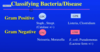

Staph vs strep

staph is catalase positive